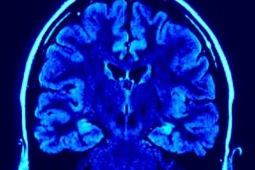

Mózg lubi niebieskie światło

Szwedzcy badacze doszli do wniosku, że fale światła niebieskiego mogą być stosowane do poprawienia funkcji poznawczych i zwiększenia poziomu energii. Ich zdaniem światło wpływa pozytywnie na mózg i poprawia ogólne funkcje psychomotoryczne oraz czujność.

Naukowcy podczas badania porównywali działanie światła niebieskiego z kofeiną. Doszli do wniosku, że światło może zaopatrzyć ludzi w energię wystarczającą na cały dzień.

Wcześniejsze analizy sugerowały, że ekspozycja światła niebieskiego, zwłaszcza przed pójściem spać, może zaburzać rytm snu, m.in. poprzez ingerowanie w produkcję hormonów. Teraz badacze są zdania, iż światło pozytywnie wpływa na mózg i jego funkcje motoryczne oraz pomaga w poprawie pamięci, jak i sprzyja szybszemu reagowaniu na bodźce. Niemieccy lekarze opracowali nawet metodę, która wykorzystuje światło w leczeniu przewlekłego bólu. Planowane też jest użycie go do stymulowania oraz poprawy aktywności mózgu u osób niewidomych.